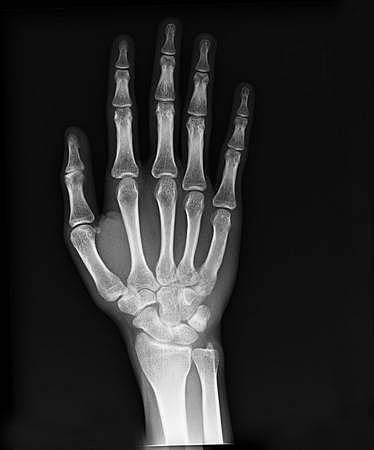

• Roentgen descubre los rayos X

Roentgen descubre los rayos X

El físico alemán Wilhelm Conrad Röntgen descubrió los rayos X en 1895, mientras experimentaba con los tubos de Hittorff-Crookes y la bobina de Ruhmkorff para investigar la fluorescencia violeta que producían los rayos catódicos.Determinó que los rayos creaban una radiación muy penetrante, pero invisible, que atravesaba grandes espesores de papel e incluso metales poco densos.

se iniciaron los estudios y aplicaciones de los rayos X en la medicina, las capacitaciones de personal y las medidas de protección para evitar el daño al personal.